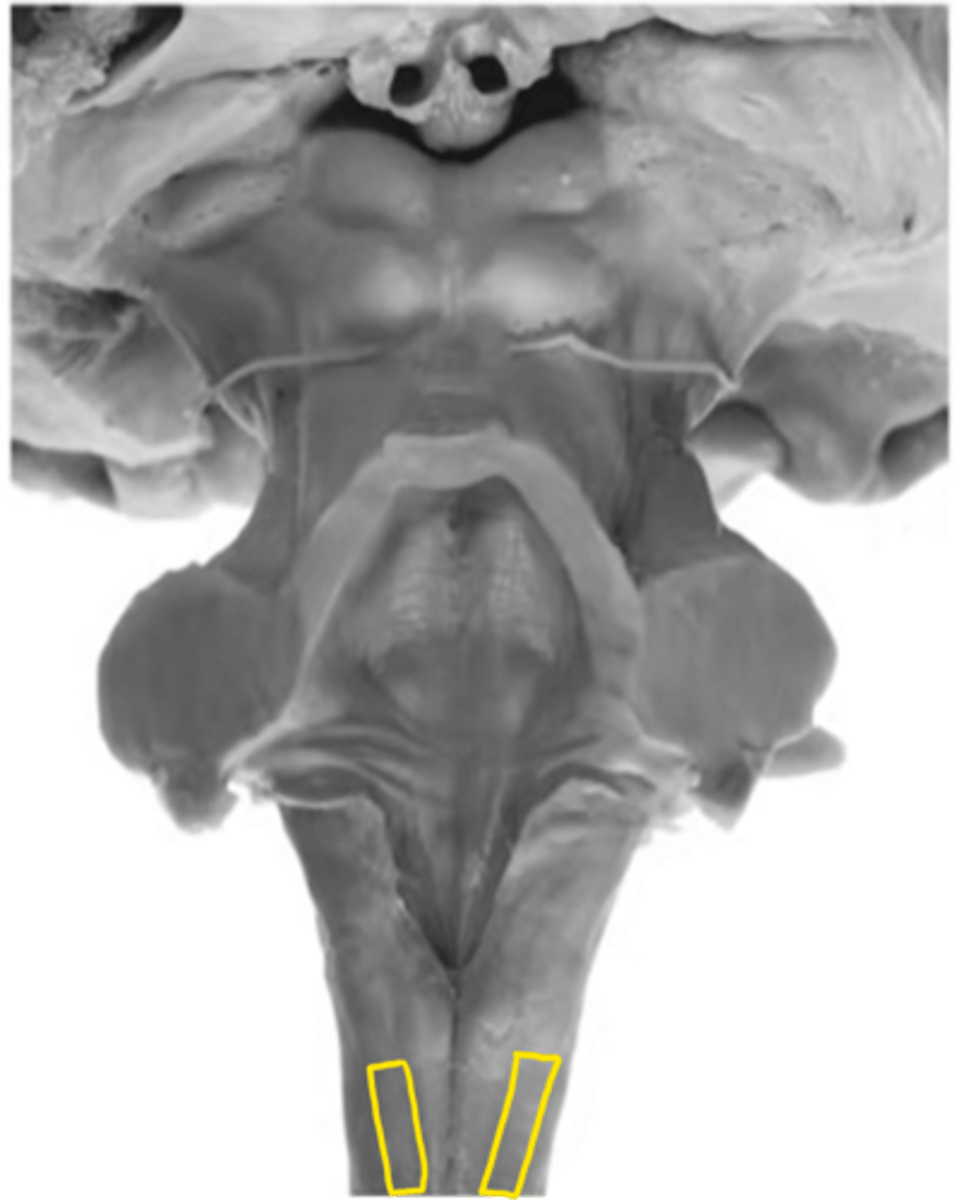

medullary pyramids

ID the structure

pyramidal decussation